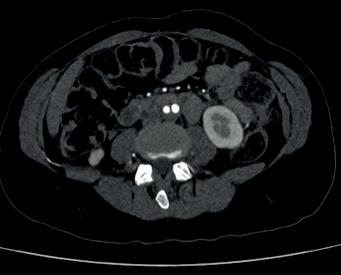

Left: Pre- and postoperative images (courtesy of Dittmar Böckler) of the first European implantation of the Gore Tag TBE; above: Dittmar Böckler performing the implantation